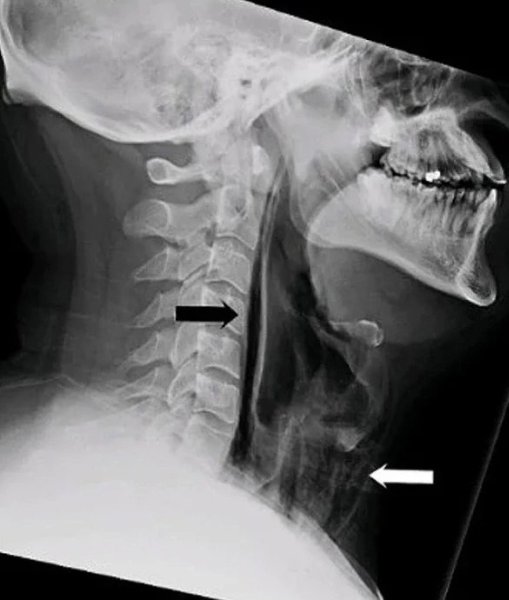

Мужчина испытал болезненные ощущения в области шеи, когда пытался сдержать чихание.

В результате чихания он ощутил «хлопок» в шее, после чего возникли проблемы с глотанием. МРТ-исследование показало, что воздух выходил через отверстие в трахее в мягкие ткани шеи. В течение нескольких дней мужчина получал питание через зонд, чтобы ткани могли зажить.

Когда мы сдерживаем чихание, воздух не может выйти наружу, и его давление разрывает мягкие ткани, причиняя им вред. Новая фобия в копилку.